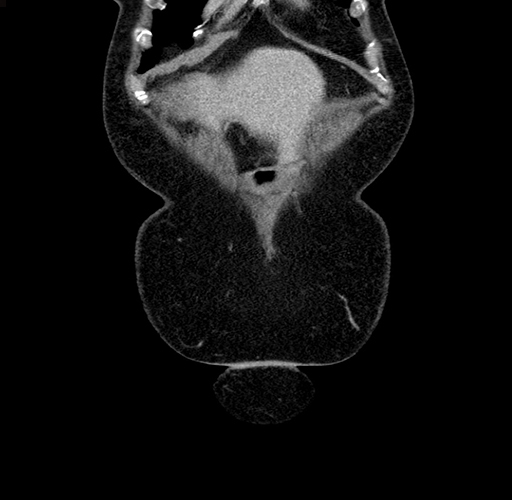

Pre-Chemo: Coronal Venous

Coronal Venous